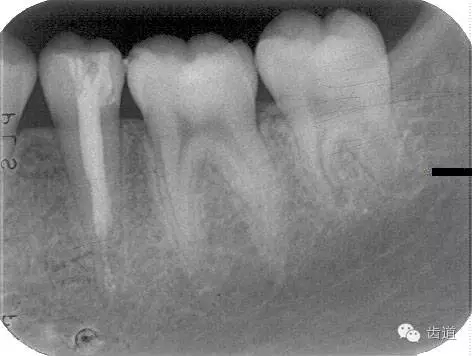

術(shù)前

術(shù)后

1. 術(shù)前X線片